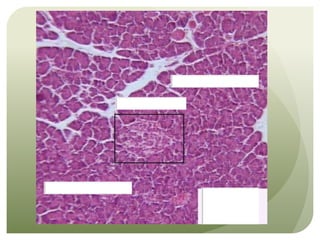

This document appears to be a brief note about an anatomy or histology lesson. It mentions an "Anatomy Bell Ringer #2" and the topic of "Histology," suggesting the document relates to a class that is covering human anatomy and microscopic tissue structures. However, the note indicates there are "Too many things to cover up" in the allotted time, implying the lesson plans to discuss multiple topics but may not have enough time to cover everything.